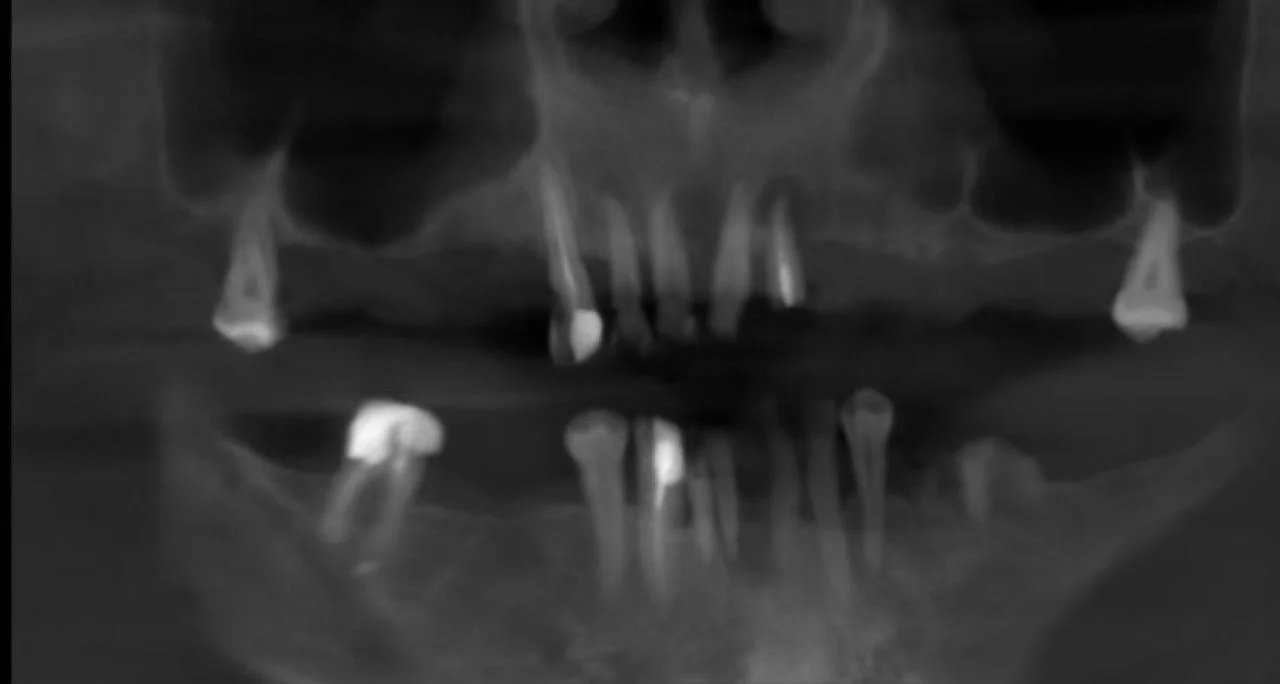

Екстракція зубів за пародонтологічними показами, все на 6-х імпл верхня та нижня щелепа, вже запротезований постійно 2 роки.